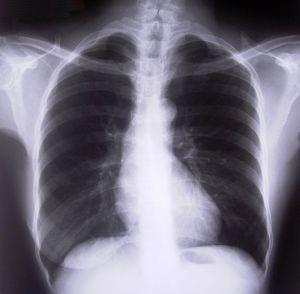

Os pulmões saudáveis

O edema pulmonar, ou também conhecido como a água acumulada nos pulmões, tem a sua origem na insuficiência cardíaca. É uma doença grave, porque é causada por uma deficiência no coração. Além disso, podem também surgir outras doenças graves como é o caso da pneumonia. No entanto o edema pulmonar tem cura, em umComo.com.br explicamos-lhe qual é o tratamento pulmonar para a água nos pulmões.